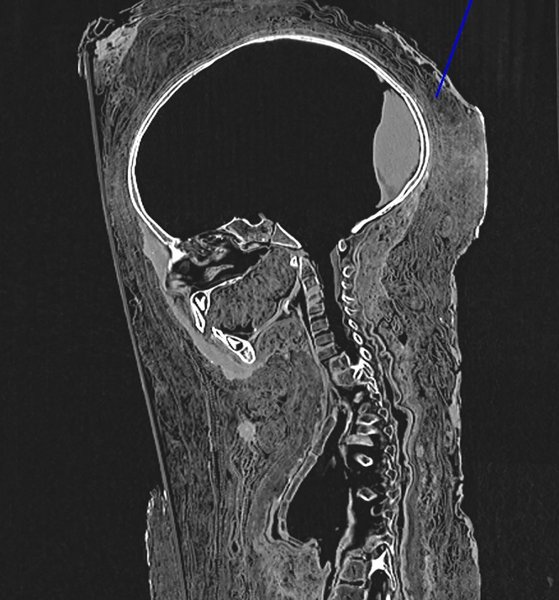

CT-scan del sarcófago sin dañarlo. ImageImageImageImage

Reconstrucción del rostro a partir del esqueleto. ImageImageImageImage